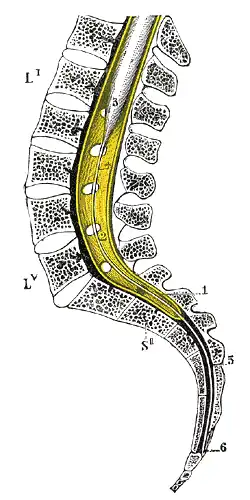

Sagittal section of vertebral canal to show the lower end of the medulla spinalis and the filum terminale. Li, Lv. First and fifth lumbar vertebra. SII Second sacral vertebra. 1. Dura mater. 2. Lower part of subarachnoid cavity. 3. Lower extremity of medulla spinalis. 4. Filum terminale internum. 5. Filum terminale externum. 6. Attachment of filum terminale to first segment of coccyx. | |

The filum terminale ('terminal thread') is a delicate strand of fibrous tissue, about 20 cm in length, extending inferiorly from the apex of the conus medullaris to attach onto the coccyx.[1][2] The filum terminale acts to anchor the spinal cord and spinal meninges inferiorly.[3]

The upper portion of the filum terminale is formed by spinal pia mater within a dilated dural sac, while the lower portion is formed by both pia and dura mater (with the outer dural layer closely adhering to the inner pial component).

The proximal/superior part – the filum terminale internum or pial part of terminal filum[3] – measures 15 cm in length and extends as far as the inferior border[1] of the second sacral vertebra (S2)[1][2] (the inferior limit sacral canal[2]). It is composed of the vestiges of neural tissue, connective tissue, and neuroglial tissue lined by pia mater.[3] It is contained within a tubular sheath of the dura mater and is surrounded by the nerves of the cauda equina (from which it can be easily recognized by its blueish-white color).[1]

The inferior/distal part – the filum terminale externum, dural part of terminal filum, or coccygeal ligament - is formed as the filum terminale internum reaches the inferior extremity of the dural sac; henceforth, the filum terminale becomes invested by a layer of dura mater.[1]

The filum terminale ultimately terminates inferiorly by attaching to the dorsum of the coccyx[3][2] at the first coccygeal segment,[1] flaring out[4] to blend with the coccygeal periosteum.[2]